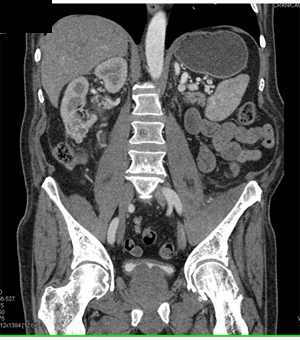

In this patient the best diagnosis for the left hip pain is?

CTisus Quiz   CTisus Quiz

metastatic renal cell carcinoma to muscle

primary sarcoma

lymphoma

abscess